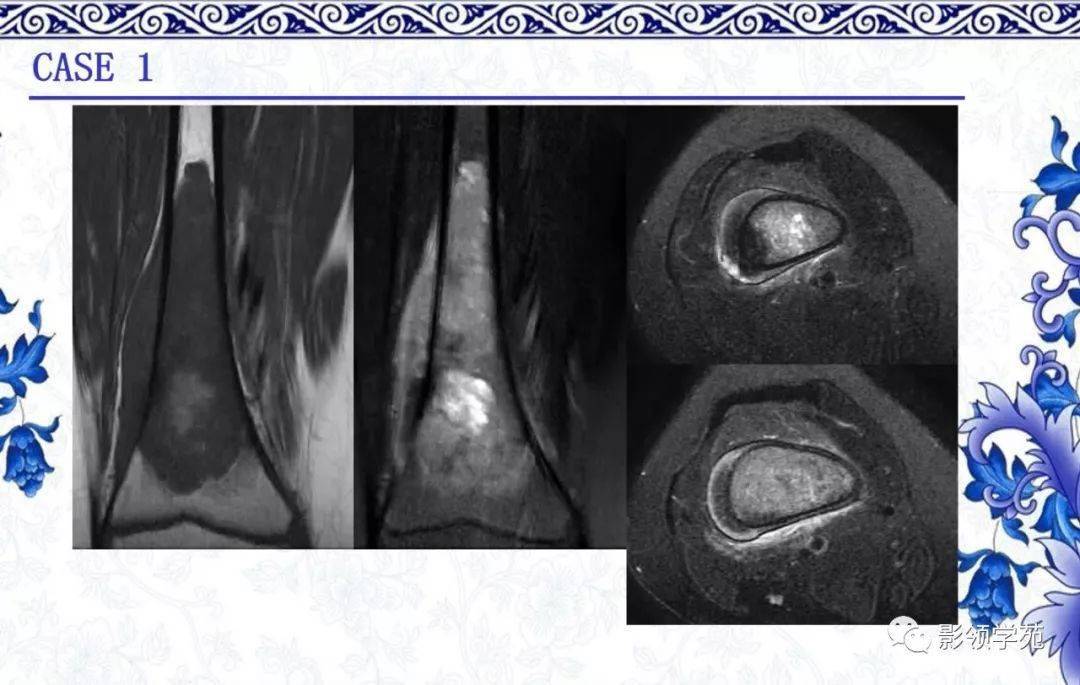

经典病例丨骨肿瘤疑难病例讨论二

图片尺寸600x729